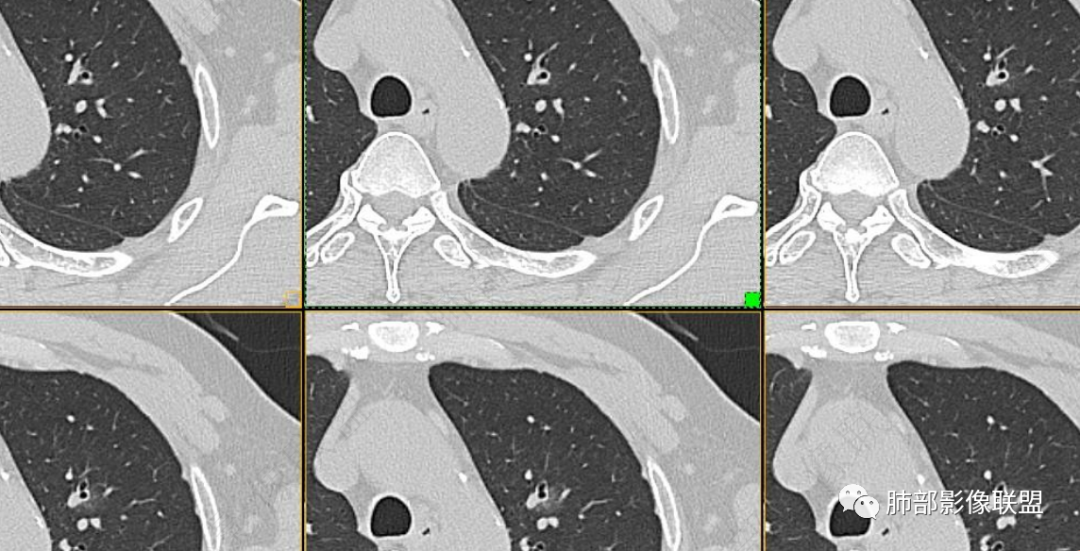

男性,肺结节3年,发现逐渐增大,影像表现,左肺舌段结节,边缘可见磨玻璃密度影,内部走形下舌段支气管变窄,增强呈持续强化,首先考虑肺腺癌,鉴别炎性肉芽肿,真菌/隐球菌。

中老年男性,发现结节,影像表现,左肺上叶结节,实性部分有膨胀性生长,边缘可见磨玻璃影,似清晰似不清晰,病灶与支气管关系密切,部分支气管似狭窄及僵硬,增强病灶强化明显,考虑腺癌(粘液性腺癌)鉴别炎性肉芽肿。

左肺上叶尖段支气管旁结节伴磨玻璃影,磨玻璃影边缘模糊,支气管走形正常,病变无明显分叶及毛刺,收缩不明显,增强呈延迟高强化。先考虑炎性肉芽肿。肿瘤待排。

左肺上叶支气管旁结节伴磨玻璃影,磨玻璃边缘略模糊,沿支气管走行,明显不均匀延迟强化,3年逐渐增大,考虑腺癌,鉴别淋巴增殖病变,炎性肉芽肿

中年男性,查体发现,左肺上叶靠近支气管旁实性结节,周围有磨玻璃影,边界清,密度高,明显强化,三年缓慢进展,考虑腺癌,鉴别类癌或炎性肉芽肿。

中年男性,体检发现左上肺结节,影像:左上肺欠规则结节+磨玻璃(边界欠清),沿支气管爬行生长,支气管无受累,增强后明显渐进性强化,3年随访增大,考虑低度恶性肿瘤,如淋巴增殖性病变,如淋巴瘤样肉芽肿可能。

左上叶结节,结节周围GGO边界模糊,短软毛刺,远端见支气管复出,纵隔窗边界平直,显著强化,良性征象较多,病程三年,综合考虑支持炎性肉芽肿,鉴别腺癌

左肺上叶尖后段结节,围绕支气管生长,周围磨玻璃影,边缘似清不清的感觉,三年病变明显增大,增强呈延迟高强化。考虑腺癌,高强化的腺癌不少见,鉴别炎性肉芽肿

中年男性,体检发现左肺上叶结节,三年逐渐长大,CT见左肺上叶部分实性结节,膨胀性生长,边缘边界清晰磨玻璃影,部分支气管狭窄,增强病灶强化明显。考虑恶性,腺癌可能。

中老年男,三年结节渐增大,边缘不太清磨玻璃密度影,明显强化,分叶、毛刺、棘突,总的恶性考虑先,腺癌鉴别肉芽肿性炎。

中老年男性,左肺上叶中轴区实性结节及周围磨玻璃影,磨玻璃边界似清非清,关键点2019.10-2021.10-2022.05结节持续增大,增强后明显强化。考虑恶性结节可能大,腺癌(黏液腺癌)?鉴别炎性结节。

361度:

1、临床:57岁男性,3年逐步增大。孤立病灶持续三年原地坐大,符合肿瘤性病变,恶性程度不高或者早期进展缓慢。良性肿瘤常多年静止或进展极其缓慢。炎性病灶“星火”可以燎原,临床表现也会逐步加重。尽管继发性肺结核可以相对惰性,但病灶强化不明显,多结节、多卫星、多新旧不等,相对清楚硬朗。

2、病灶以实性密度为主,前、外侧蔓延,GGO部分边界清楚,部分欠清

支气管未见受明显侵犯,未见阻塞,壁增厚,狭窄或扩张。

软组织+重建;病灶实性部分不是类圆形,密度相对均匀柔和。

肺门区病灶与支气管关系不密切,强化显著、磨玻璃晕等等容易想到的是肺腺癌。而不首先考虑与支气管密切相关恶性肿瘤,如鳞癌、类癌、粘液表皮样癌等等。